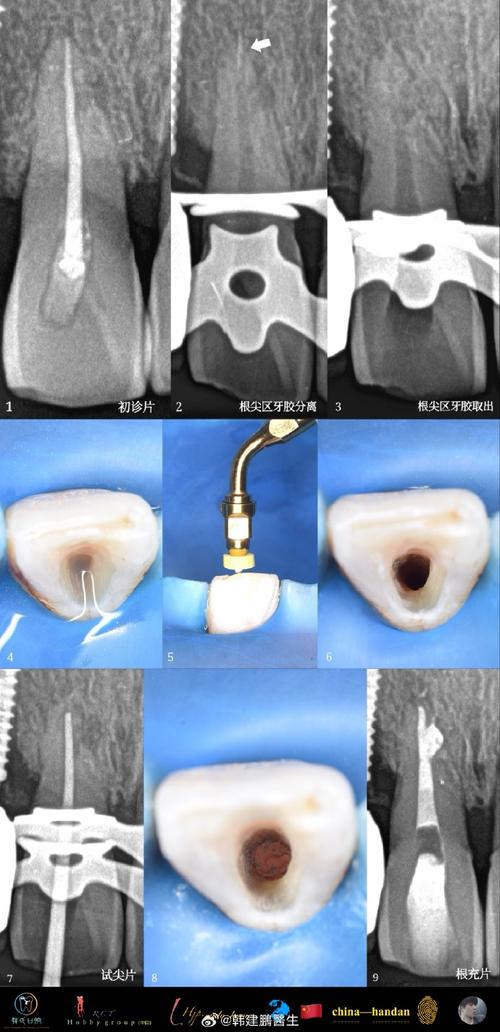

牙根吸收的诊断与监测

早期诊断是控制吸收进展的关键,临床检查中,轻度吸收多无症状,严重时可出现牙齿松动、咬合异常或牙根透暗影。X线检查是主要诊断手段:根尖片可清晰显示牙根长度变化(如牙根尖端变钝、轮廓模糊);曲面断层片用于筛查全口牙根情况;CBCT(锥形束CT)则能三维评估吸收部位、范围及程度,尤其适用于复杂病例。

正畸治疗中需定期监测:通常在治疗开始前、治疗中每6-12个月、拆除矫治器后拍摄根尖片,对比牙根长度的动态变化,若吸收速率加快(如每半年缩短>1mm),需及时调整治疗方案。